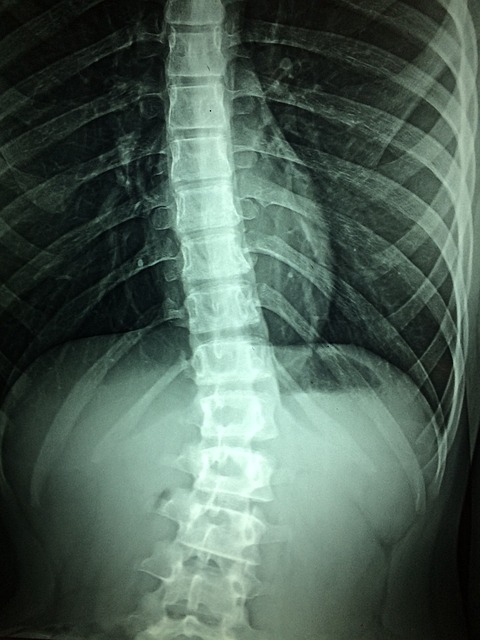

The shoulder is composed of 3 bones: the humerus (upper arm bone), scapula (shoulder blade), and the clavicle (collarbone). The upper bone’s head fits into the shoulder blade’s rounded socket. The socket is known as the glenoid.

A combination of tendons and muscles keeps the arm bone centered in the shoulder socket. The tissues are known as rotator cuff. The rotator cuff covers the head of the upper arm bone and attaches it to the shoulder blade.